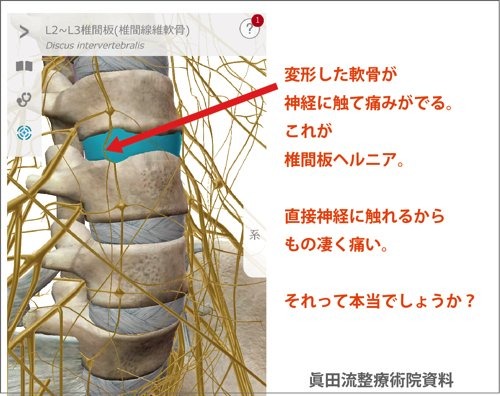

さらに詳しく椎間板が変形して飛び出し(ヘルニア)になるメカニズムを解説します。

大腰筋が腰椎を下方向に引っ張っただけで椎間板が圧迫されヘルニアになるのか?と疑問を持つ方もおられるかと思いますので少し細かく解説しますね。

これがヘルニア発症のメカニズ�

そしてもう1つ。腰椎(腰骨)の同じ部分に多裂筋という背骨に沿った筋肉も付着しています。

多裂筋

起始:仙骨背面、後仙腸靱帯、腰椎の乳様突起、胸椎の横突起、C4-7の頚椎関節突起

停止:2-4個上の椎骨の棘突起

働き:腰部の伸展運動・同側への側屈運動・対側への体幹回旋運動

この多裂筋は首コリや肩こりの酷い方は硬直している場合が多く、デスクワークの方には顕著に硬直が見られます。

多裂筋に硬直により上と下に引っ張り合う

硬直した筋肉は固くなり縮む習性がありますので、多裂筋の硬直により背中が凝る(固まる)または上方向に腰椎を引っ張る状態が発生します。

この状態で大腰筋が硬直すると大腰筋が腰椎の付着部分を下方向へ引っ張るので多裂筋と上と引っ張りっこになり間の椎間板が耐えられず飛び出してヘルニアになるのです。

拡大してみてみるとこのようになっています。

この状態なら骨と骨の間に圧力が加わって軟骨が飛び出すのも納得ですし、他のどのヘルニアの原因解説よりも整合性があると思います。

医学的に椎間板ヘルニアの痛みは、変形して飛び出した軟骨が周辺の神経に触れるから痛いとされています。

整体眞田流では椎間板ヘルニアの診断が出ているお客様に必ず確認するのは

飛び出している軟骨やその周辺を触って痛みがあるか?

ヘルニア部分を軽く叩いて痛みがあるかを確認します。

飛び出して神経に触れているとされる軟骨周辺を軽く叩いても痛みが増したり脚の痺れが強くなりこともなければ真正の椎間板ヘルニアでは無いと考えられます。

飛び出した軟骨が神経に当たるから腰に痛みが出ている筈なのに、軟骨と神経が当たっている部分を叩いても痛くないという事は辻褄が合いません。